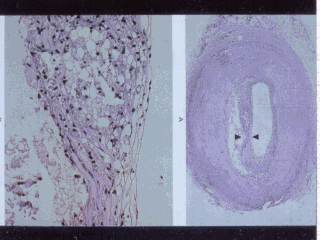

slide shows an atherosclerotic plague with in the bottom half an enlargement of the

shoulder region of the plague. Large numbers of inflammatory macrophages may play a role

in plague vulnerability to rupture and the precipitation of the acute event. The